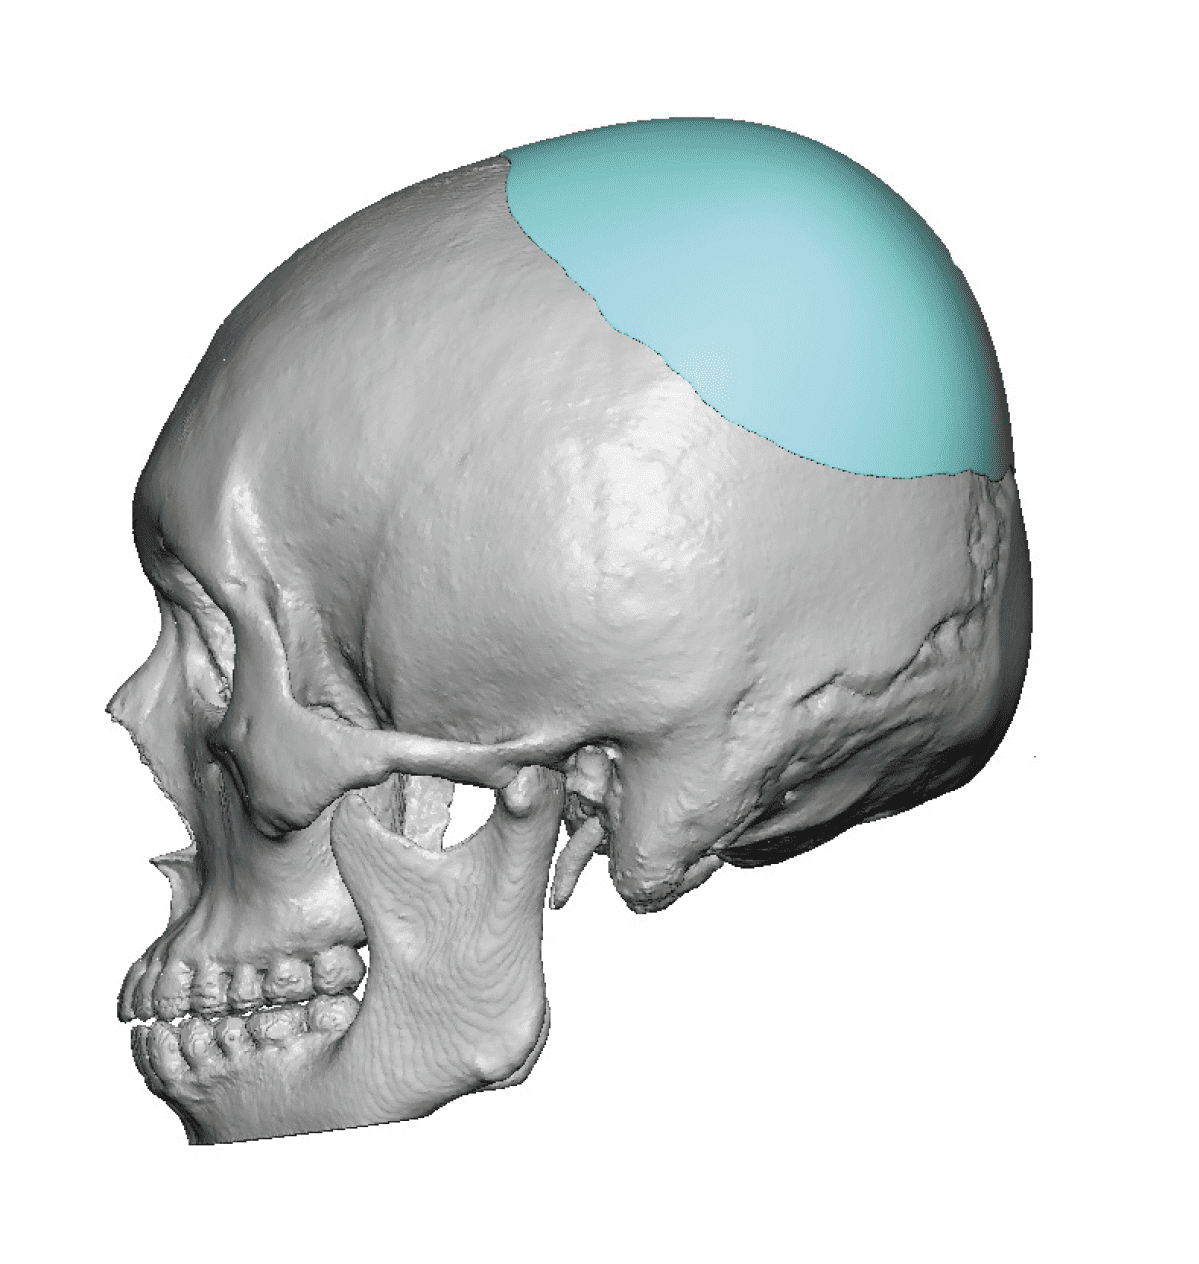

Desire for a higher and more prominent crown of the skull.

Crown of skull augmentation using a custom skull implant.

Desire for a higher and more prominent crown of the skull.

Crown of skull augmentation using a custom skull implant.